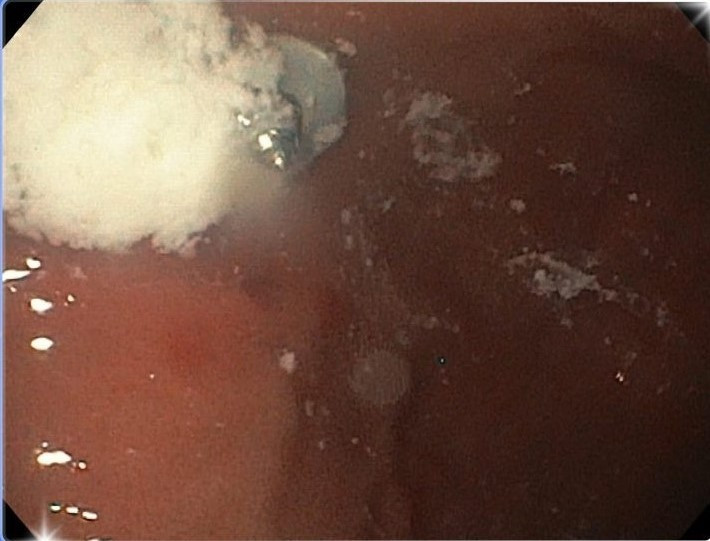

Ngay sau đó, các bác sĩ khoa Nội soi đã nhanh chóng thực hiện nội soi gắp dị vật có gây mê cho bé.

Nhờ sự hỗ trợ của hệ thống nội soi tích hợp camera hiện đại, một chiếc ốc vít với kích thước 5x6mm, đầu sắc nhọn đã nhanh chóng được bác sĩ gắp ra.

BS.CKI Trương Minh Hiếu, Trưởng khoa Nội soi, người trực tiếp thực hiện ca gắp dị vật chia sẻ: “Quá trình nội soi gặp không ít khó khăn vì dị vật trơn, hình tròn, lại lẫn với bã thức ăn khiến việc thao tác trở nên phức tạp.

Tuy nhiên, nhờ trang thiết bị hiện đại và sự phối hợp nhịp nhàng của ê-kíp, chúng tôi đã xử lý thành công, đưa dị vật ra ngoài an toàn mà không gây tổn thương đến các cơ quan lân cận”.

Nội soi gây mê lấy ốc vít cho trẻ - Ảnh BVCC